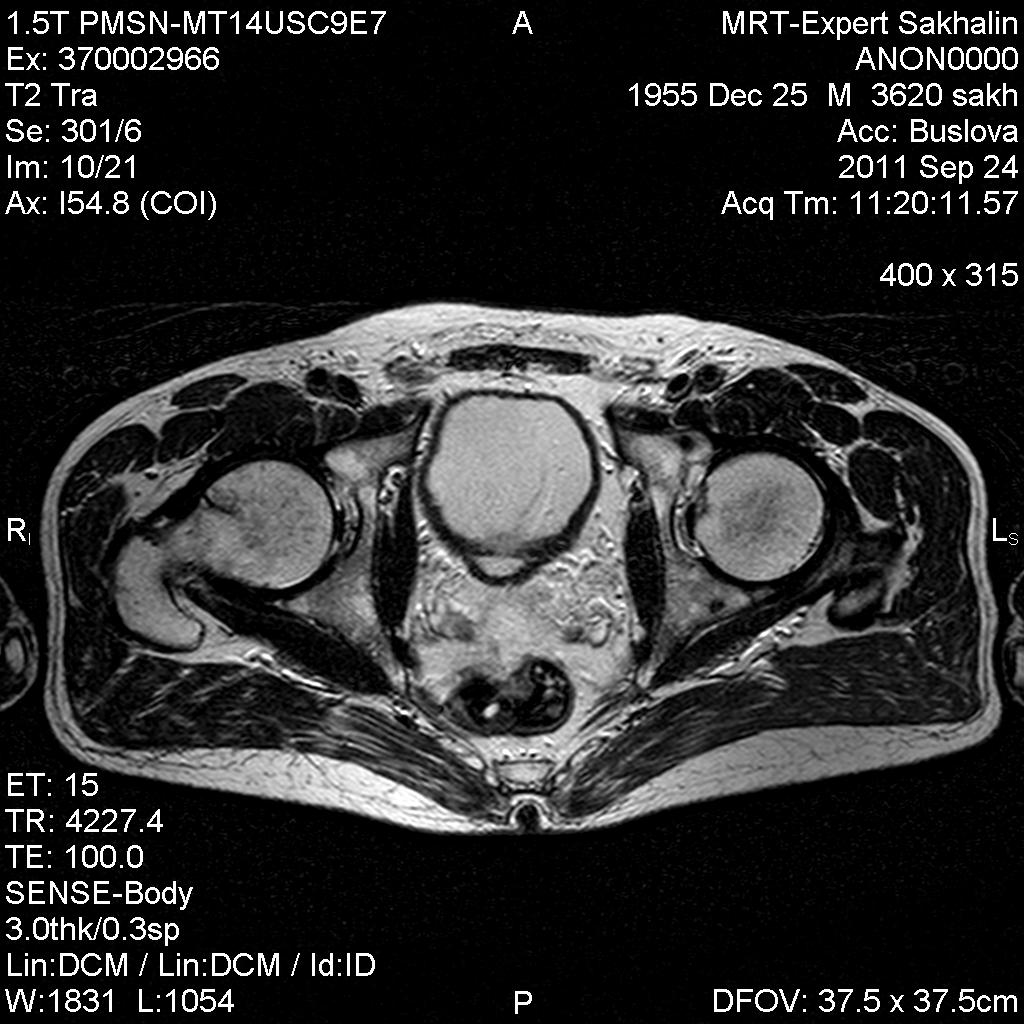

Мужчина пришел на МР-исследование правого тазобедренного сустава.Рентгенограммы также принес( удивительно- скорее,исключение,чем норма). Пока выставляю рентенограммы завтра МР-картинки.

У мужчины уже лет 5 назад были выявлены склеротические очаги в подвздошной и бедренных костях, тогда же подозревали бластические метастазы, но обследования показали норму ( судя по записям в амбулаторной карте).

А вот про очаг в шейке данных не было.

Добавила МР-картинки.

В подвздошной кости фокус аинтенсивный , без перифокальной реакции, учитывая сигнальные характеристики  и отсутствие  динамики -бесструктурный очаг обезыствления.В голове бедренной кости очаг с характеристиками жидкостного характера, четким, неровным контуром, без перифокального отека- кистовидая перестройка ?

Irena пишет о головке правого бедра? То, что в шейке бедра не киста разве?  А слева нормальная головка?

Слева ничего особенного в головке не вижу.

В головках, подвздошных костях  есть мелкие  склеротические очажки, участки жировой дистрофии.В шейке скорее всего,киста, конечно.